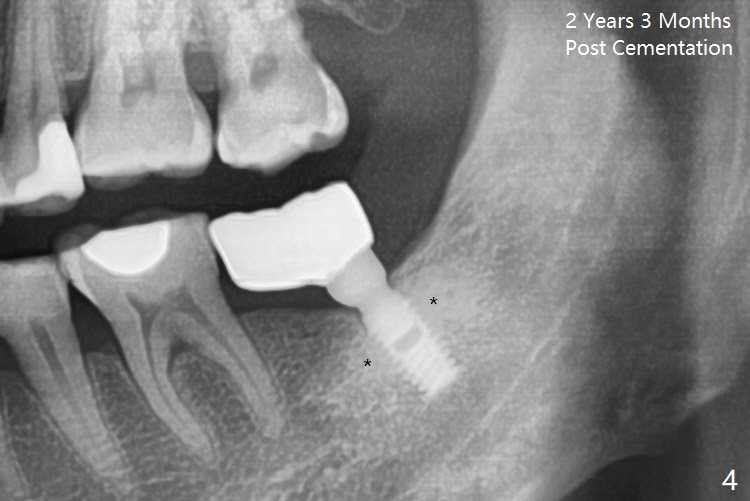

A 4.5x8 mm Bicon implant is placed (Fig.1-3) with intent to intrude the supraerupted opposing tooth once a provisional is fabricated. Now it is 5 months postop. In spite of poor implant position, the abutment or the crown has not become loose with increased bone density around the implant 2 years 3 months post cementation (Fig.4: *). Guide could easily overcome the deficiency.